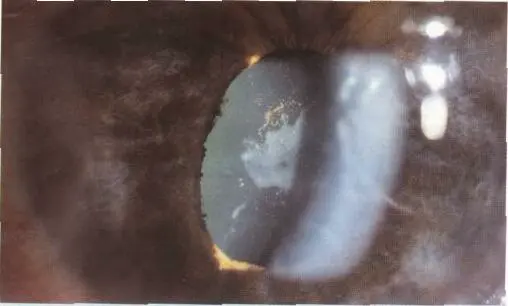

Immature cat

- Diagnosis: Immature senile cataract